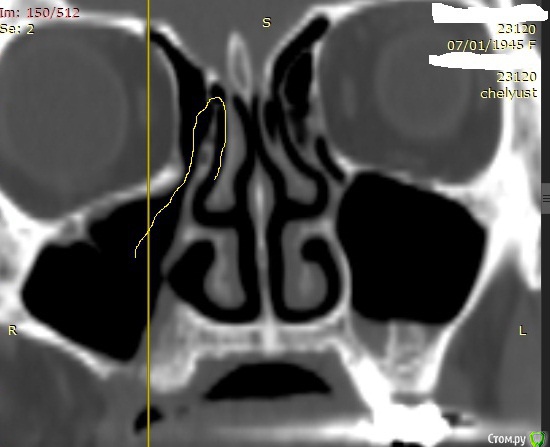

Alexey Doc Опубликовано 29 апреля, 2015 Поделиться Опубликовано 29 апреля, 2015 В клинику с целью протезирования обратилась пациентка 70 лет.Ортопед направил на консультацию. В анамнезе: со слов больной год назад удален зуб 1.6 после чего сформировался оро-антральный свищ. В январе 2015 года выполнена правосторонняя радикальная гайморотомия с удалением 1.5, 1.7 зубов. Сопутствующая патология в стадии компенсации.На сегоднещний день жалоб кроме отсутствия зубов нет.В полости рта : верхний свод преддверия справа плавно перетекает в небо мощным тяжем подвижной слизистой шириной примерно 15-17 мм . Альвеолярный отросток отсутствует. Какой\ие минимально инвазивные( учитывая возраст пациентки) способы аугментации вы бы применили у этой больной для последующего протезирования с опорой на имплантатах? Буду рад любому мнению и рац.предложению.Ниже свежие срезы КТ. Ссылка на комментарий

Alexey Doc Опубликовано 30 апреля, 2015 Автор Поделиться Опубликовано 30 апреля, 2015 ткните пальцем не вижу что то)Хорошо проходимая решетчатая воронка Ссылка на комментарий

Alexey Doc Опубликовано 30 апреля, 2015 Автор Поделиться Опубликовано 30 апреля, 2015 Бабуля может еще 30 проживет...Я за зигомыЗигомами не владею.Вот еще пара картинок реконструкции Ссылка на комментарий